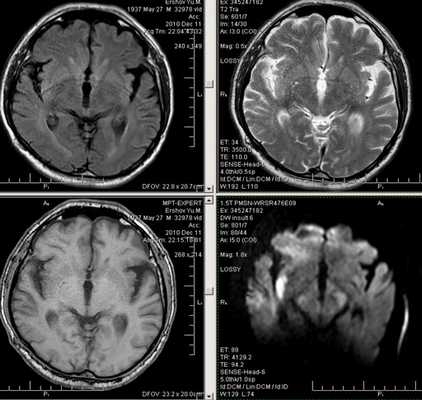

Одним из наиболее информативных среди современных методов нейровизуализации является метод МРТ диагностики.

Только благодаря современным программам, используемым в МРТ диагностике, стало возможным распознавание признаков нарушения мозгового кровообращения уже в первые 24 часа.

Первые часы ОНМК. Изменения в области правого островка демонстрирует только программа DW insult.